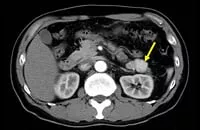

CT画像(インスリノーマ例)**

**:腫瘍を矢印で示す